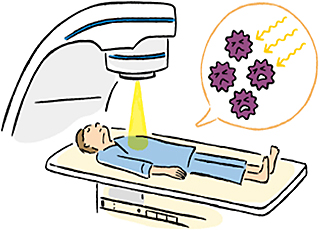

放射線治療

腫瘍に放射線を当てることで腫瘍細胞を傷害し、腫瘍を小さくする治療です。

1.セミノーマ(精上皮腫)

放射線治療が特に有効で、Ⅰ期のセミノーマの再発予防のためとⅡ期のセミノーマの比較的小さなリンパ節転移に対して行われることがあります。

2.非セミノーマ(非精上皮腫)

放射線治療の効果があまり期待できないため、初期治療として選択されることはありません。